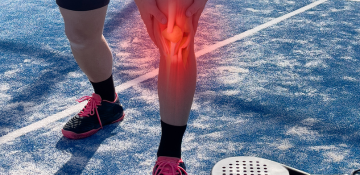

Αθλητικές Κακώσεις

Αντιμετώπιση τραυματισμών σε επαγγελματίες και ερασιτέχνες αθλητές με στόχο την πλήρη λειτουργική αποκατάσταση και ασφαλή επιστροφή στην αθλητική δραστηριότητα.